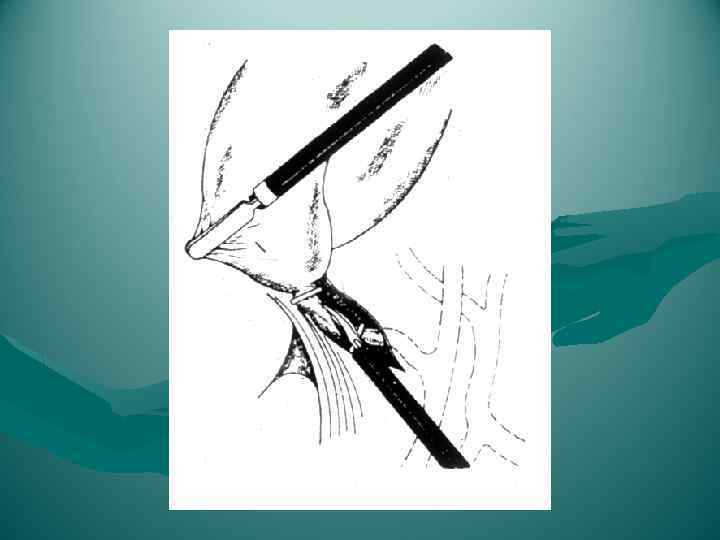

ПЕРЕВЯЗКА ОБРАЗОВАНИЙ В ВОРОТАХ ЛЕВОЙ ДОЛИ ПЕЧЕНИ

ПЕРЕВЯЗКА ОБРАЗОВАНИЙ В ВОРОТАХ ЛЕВОЙ ДОЛИ ПЕЧЕНИ